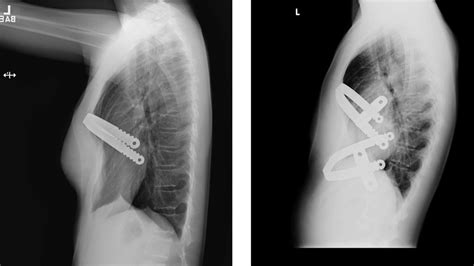

800×533

venturamedicaltechnologies.com

Pectus Up implant on a patient after Nuss Bar removal - Ventura Medical ...

576×774

academia.edu

(PDF) An uncommon complication of Nu…

664×950

researchgate.net

3 months after removal of Nus…

670×906

Right after removal of Nus…